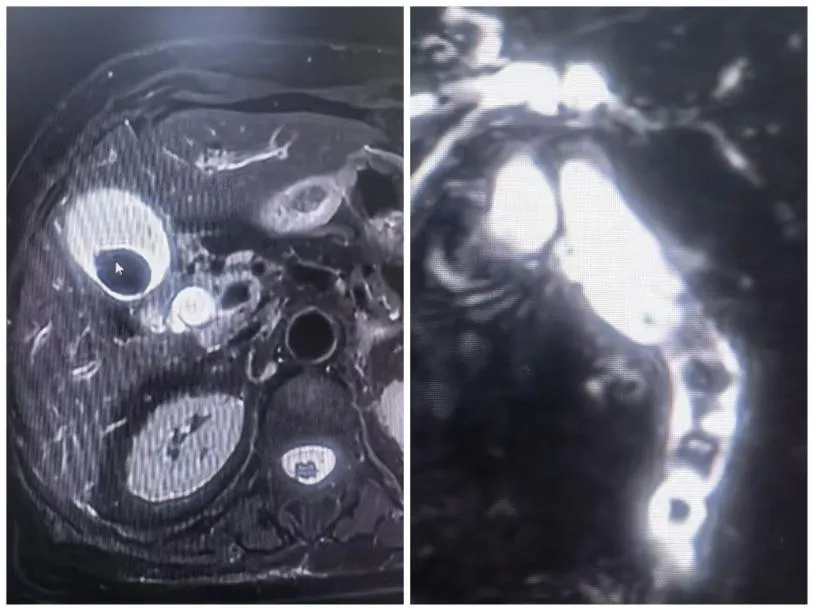

老人被紧急转运来时,情况十分危急:不仅胆囊多发结石合并急性胆囊炎,而且患有充满性胆管结石,引发了凶险的急性阻塞性化脓性胆管炎---重症胆管炎;如不能得到及时有效的救治,死亡率极高。

更让人揪心的是,老人身体基础条件差,合并多种基础病——血小板极低(仅37×109)、冠心病、高血压、脑梗死、肝囊肿等。

术中,打开胆管瞬间,大量脓性胆汁溢出,手术团队在保证治疗效果的前提下,最大程度减少了对老人身体的创伤,让他顺利度过难关。